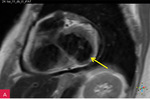

Rycina 7A-D. Obrazy rezonansu magnetycznego w osi krótkiej na wysokości pierścienia mitralnego: czarnej krwi T1-zależne TSE (A); czarnej krwi T2-zależne HASTE (B); T1-zależne echa gradientowego dynamicznie podczas podawania środka kontrastowego (C); sekwencja SSFP, pojedynczy obraz w osi krótkiej (D). W dolno-bocznej części pierścienia mitralnego od strony światła lewej komory zmiana (strzałki) niskosygnałowa we wszystkich ważeniach sygnału

W celu weryfikacji zmiany i oceny charakterystyki tkanki wykonano CMR,

w którym stwierdzono w dolno-bocznej części pierścienia mitralnego od strony światła lewej komory zmianę odpowiadającą morfologicznie CCMA, obejmującą 7,3 cm obwodu pierścienia mitralnego, o grubości w osi krótkiej do 25 mm, w osi długiej do 21 mm; zmiana ulegała brzeżnemu wzmocnieniu kontrastowemu i powodowała ograniczenie ruchomości tylnego płatka zastawki mitralnej, obejmowała struny ścięgniste mięśnia brodawkowatego tylno-przyśrodkowego. Ponadto uwidoczniono znacznie powiększone przedsionki z istotnym włóknieniem – jak w restrykcji (ryc. 7, 8).